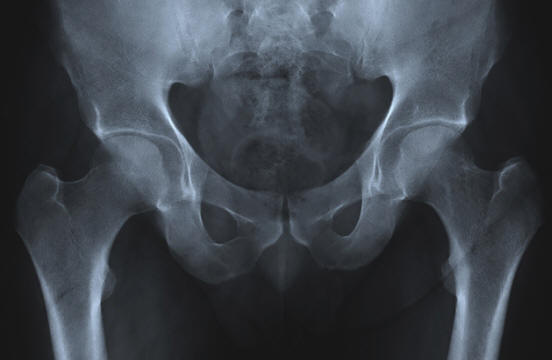

Szuper sűrű csontok

fénykép nyílt forrásokból

Az öregedés elkerülhetetlenül a fizikai tömeg megjelenésével jár problémákat. Gyakori példa az oszteoporózis, a csontvesztés és a sűrűsége. Elkerülhetetlen, törött csonttörésekhez vezet csípő és kiálló gömbök. Azonban egy embercsoport rendelkezik egy egyedülálló gén, amelyben rejlik az oszteoporózis kezelésének titka.

Ezt a gént Afrikaners (Dél – afrikai kórokozók) populációjában találták Holland származás). Ez ahhoz a tényhez vezet, hogy az emberek növeli a csonttömeget az élet során, és nem elveszíti őt. Pontosabban, ez egy mutáció a SOST génben, amely szabályozza a fehérjét (szklerosztin), amely szabályozza a csontok növekedését.

Ha egy afrikáner mutáns gén két példányát örökli, akkor megkapja szklerózis rendellenesség, amely csont proliferációhoz vezet szövet, gigantizmus, arc parézis, süketés és korai halál. Nyilvánvaló hogy ez a rendellenesség rosszabb, mint az osteoporosis. De ha Afrikaner örököl a génnek csak egy példánya, sűrű csontokat kap az egész számára élet.

Bár jelenleg ennek a génnek az előnyei vannak felhasználva csak a heterozigóta hordozói, a tudósok vizsgálják az Afrikaners DNS-ét remélve, hogy talál módszereket az oszteoporózis és mások visszafordítására csontváz rendellenességek. A már megszerzett ismeretek alapján a tudósok megkezdték a szklerosztin-gátló klinikai vizsgálatát, amely képes stimulálni a csontok kialakulását.